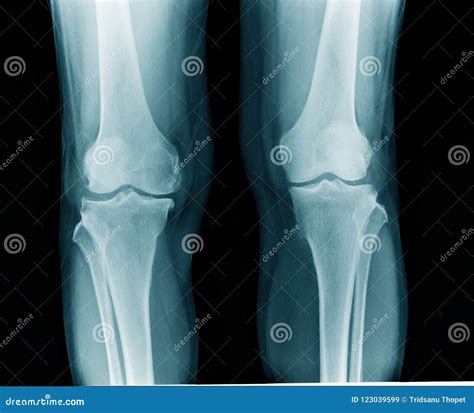

Diagnosing artritis en la rodilla involves a combination of medical history, physical examination, and diagnostic tests. The diagnostic process typically includes:

• Imaging Tests: X-rays, MRI, or CT scans may be used to visualize the knee joint and assess the extent of damage.